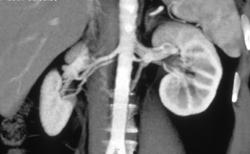

Focal Renal Artery Stenosis